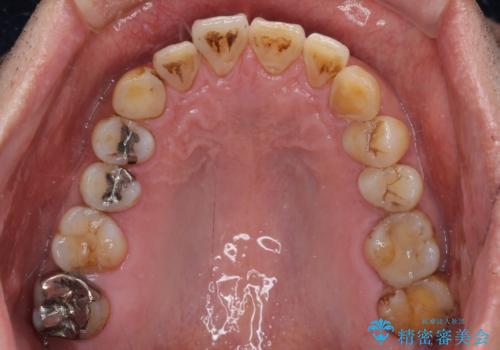

- 銀歯やインレーが外れたまま放置された奥歯の治療を希望して来院された患者様です。

咬合力が著しく強いため、欠損の多い歯はフルジルコニアクラウンへ、その他の虫歯はゴールドインレー(PGAインレー)にて修復することとしました。

来院時は全てセラミックでの治療を希望されていましたが、歯列や咬み合わせから咬合力による破損リスクが高いと判断されたため、ゴールドインレーを選択しました。